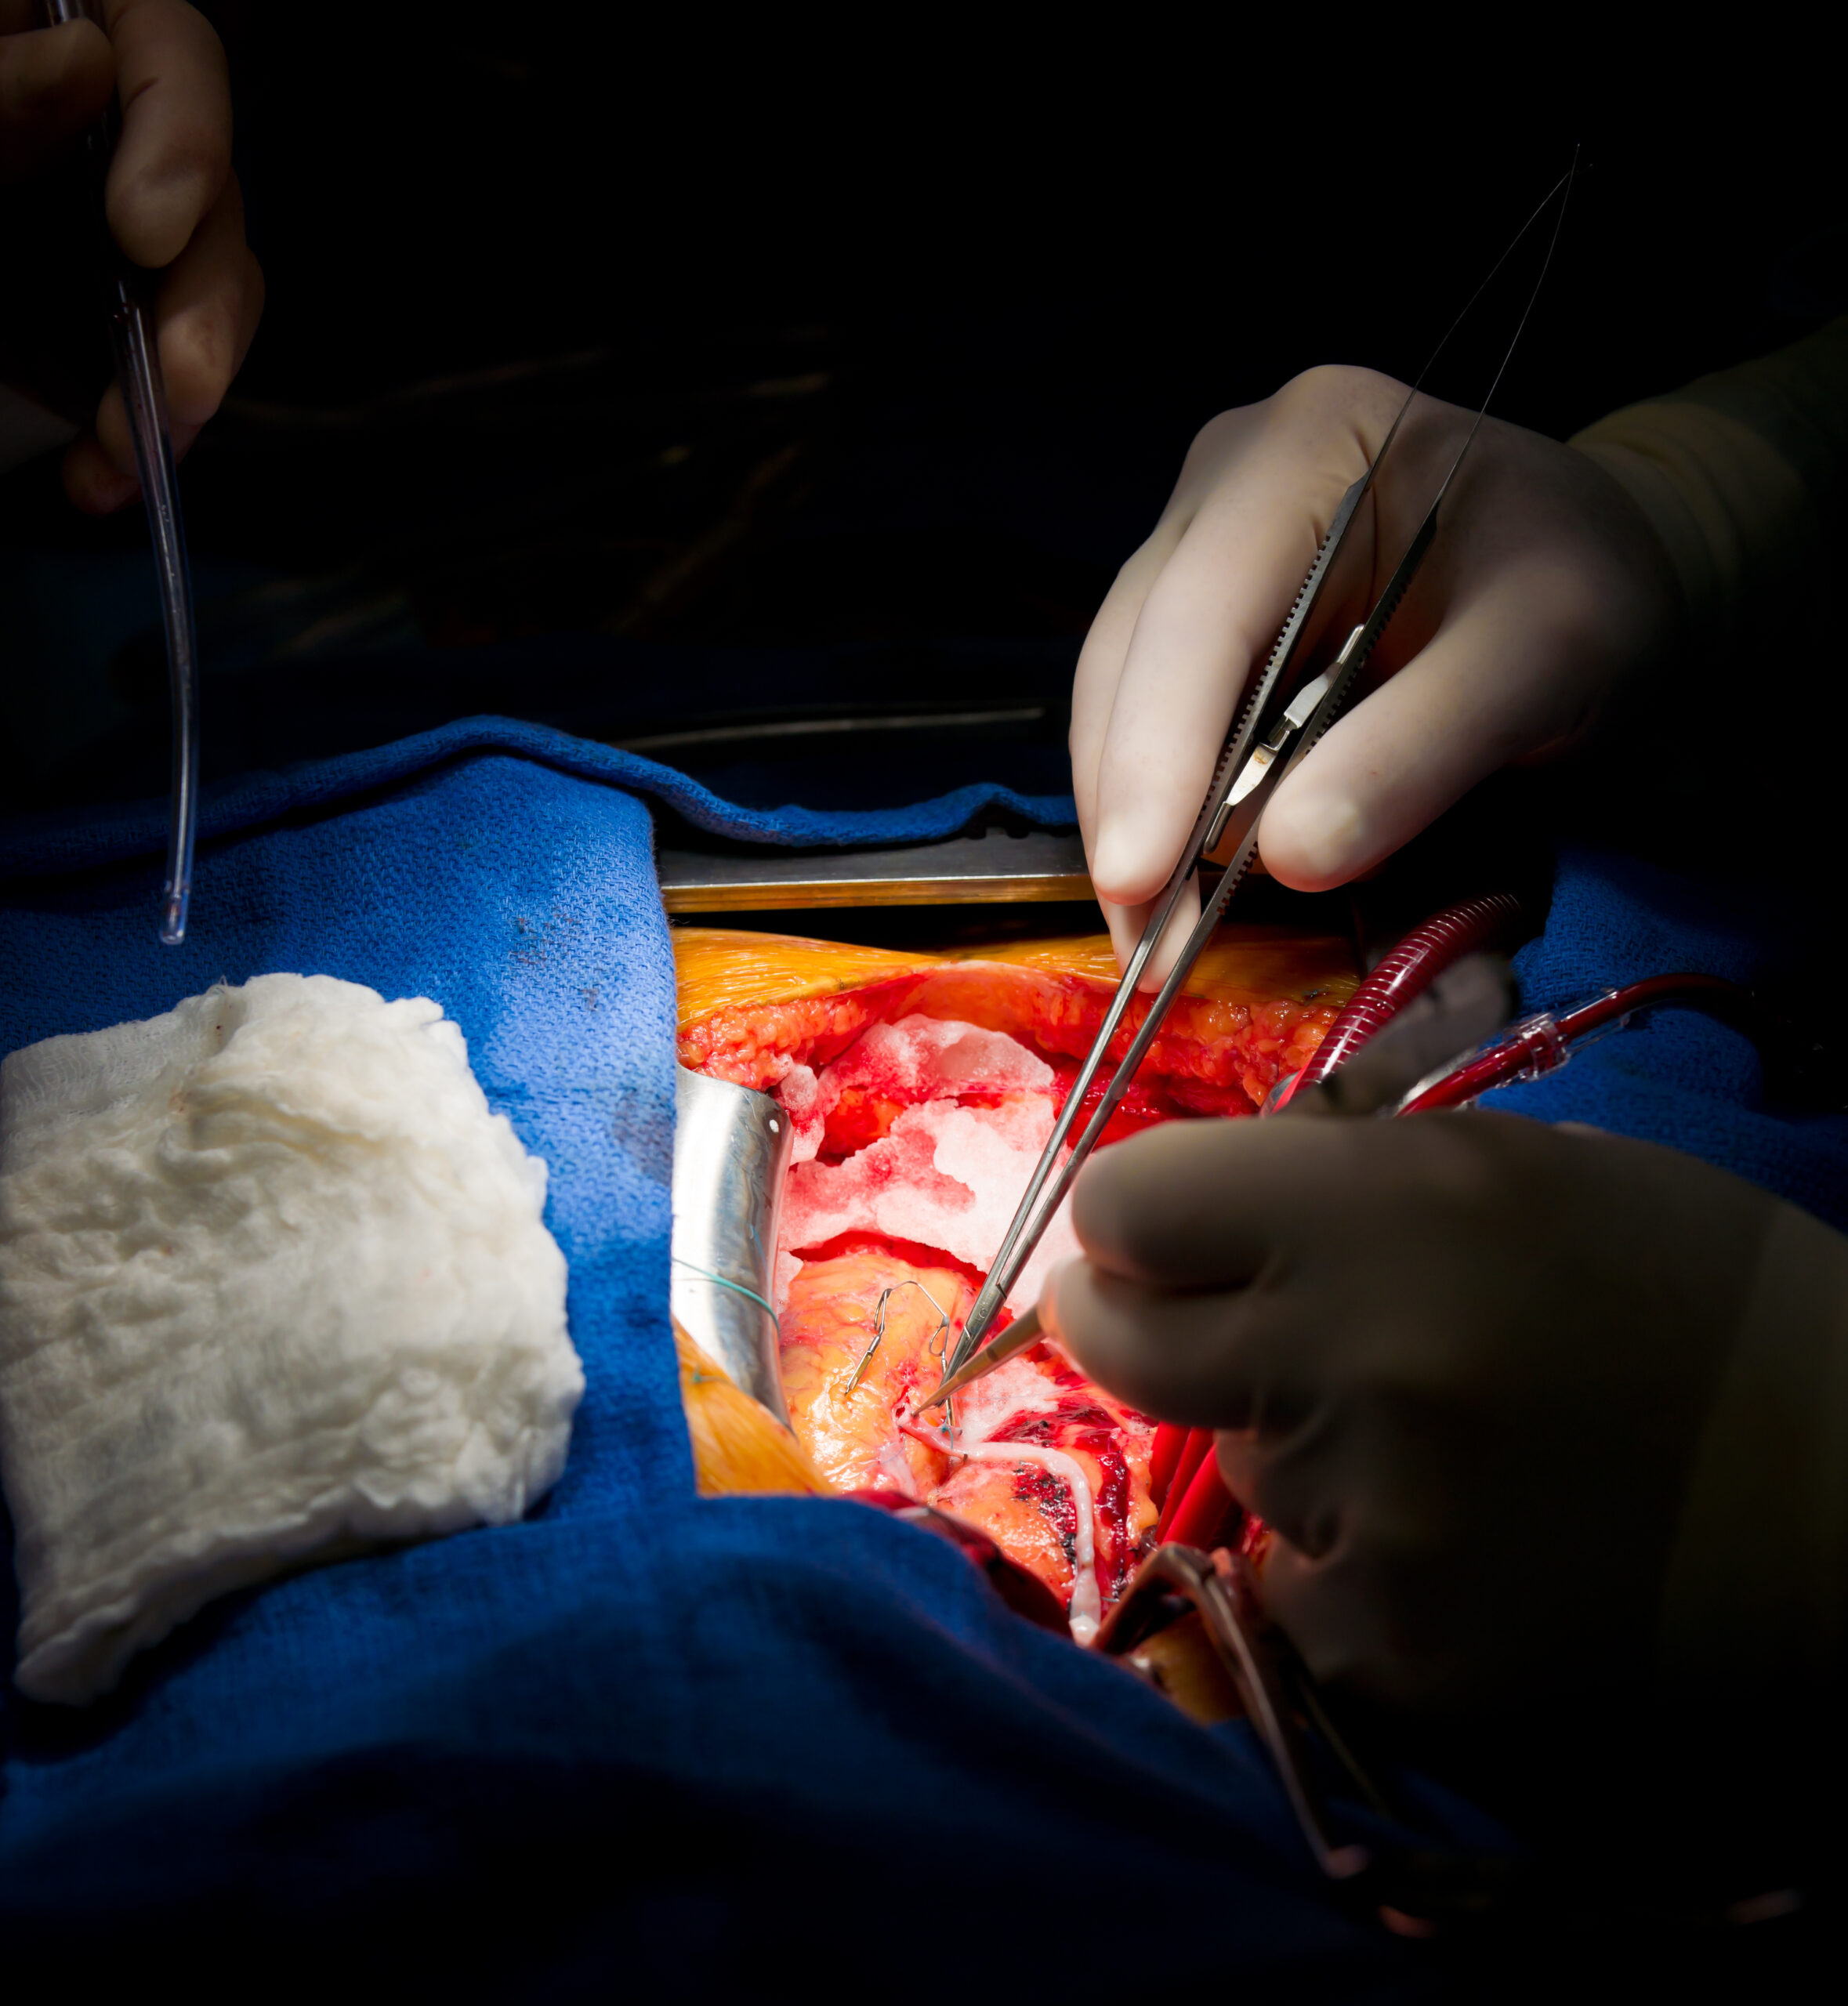

In patients with a coronary artery bypass graft (CABG) procedure prior to an acute coronary syndrome, alirocumab added ...